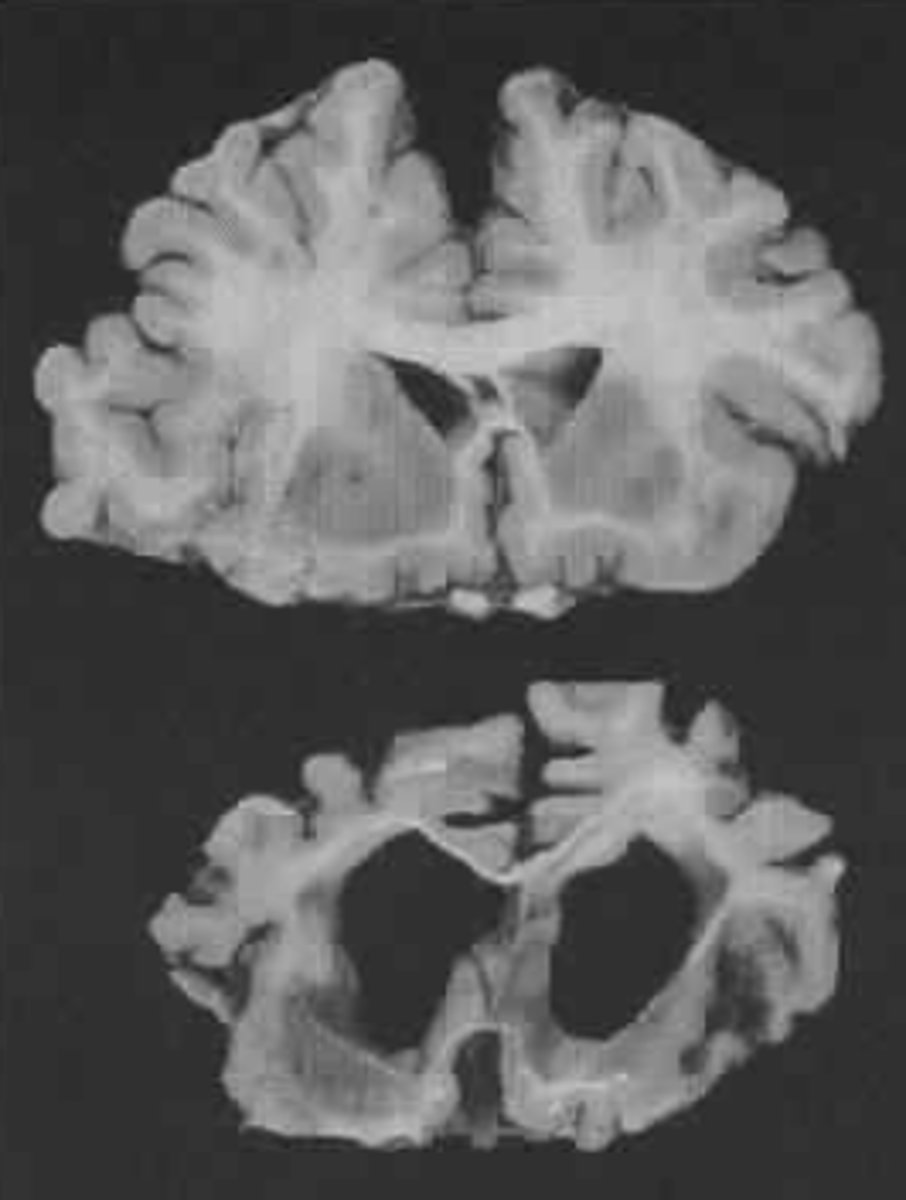

1. Normal pressure hydrocephalus

Increase in intra-cranial pressure due to accumulation of cerebrospinal fluid

What may occur in the later stages of frontal lobe damage?

Urinary incontinence

What may urinary incontinence in people with frontal lobe damage lead to?

Urinary "indifference"